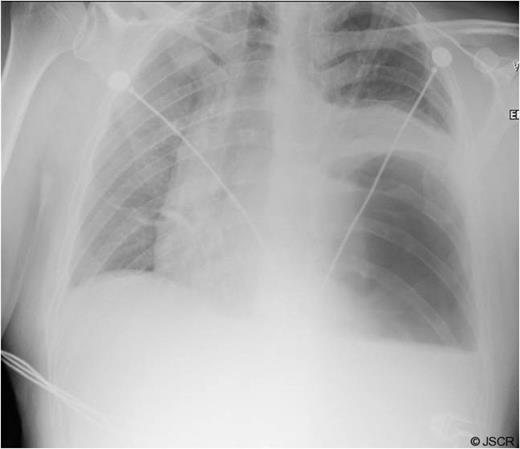

Chest pain persisted and the patient required higher pressure CPAP to maintain adequate oxygenation. Auscultation consistently showed decreased air-entry in the lung bases. On day 3, a repeat chest x-ray showed a left lower lobe collapse above the gastric bubble in the mid zone of the chest (Fig. 4 & 5). CTPA done on the same day to exclude pulmonary embolism confirmed a para-oesophageal hernia that was pushing against the left lung base. Ultrasound scan of the left chest also showed movement of the diaphragm below the gastric bubble.

Post-op CT-scan demonstrating the left sided pleural effusion with collapse /consolidation & patchy opacification on the right side.